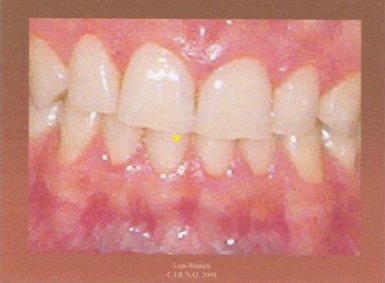

1.- Es conveniente adiestrar al paciente para que aprenda a realizar lateralidades izquierda y derecha desde su máxima intercuspidación. También es aconsejable poner un separador labial. Tras secar los incisivos superiores e inferiores con un rollo de algodón, marcamos un punto en la arcada inferior con el rotulador.

2.- Adherimos un trozo de papel celo a los incisivos superiores.